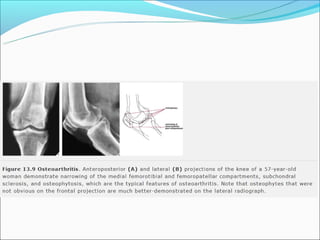

Osteofitóse

Esclerose

Redução do espaço

articular